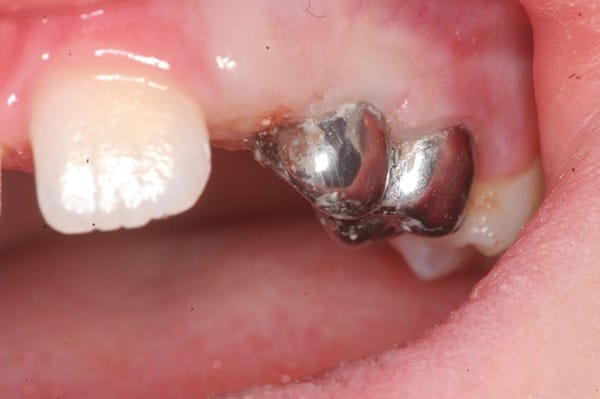

Mi hijo desde que le salieron los primeros dientes ha tenido problemas en ellos (caries, molestias).. Según los médicos por la cefalexina, ampicilina y otros que me suministraban en el embarazo y luego a el cuando nació amoxicilina.. Ha sido un martirio desde muy pequeño en el odontólogo... :'( pero lo que me preocupa comenzó hace poco mas de un año, me dijeron que tenia una caries grande en una muelita y que le debían hacer endodoncia o algo así, la cosa fue que le abrieron un hueco a la muela y le metieron un algodón con medicamento y se lo dejaron ahí como 2 meses mas o menos y el niño se quejaba constantemente pero la odontóloga decía que era normal pero le salio una bola grande en el colmillo del lado de la muela tratada la cual estaba llena de pus... Igual me seguían diciendo que no era nada grave y en la muela en esos dos meses no le hicieron revisión ni nada...

Luego este año en los primeros días de enero le volvieron a realizar lo mismo (hueco, algodón, medicamento) y lo volvieron a cerrar.. En este caso también sentía molestia y lloraba mucho, le volvió a salir la bola en el colmillo del lado pero ahora mas grande y a parte también le salio otra en la muela de atrás (la que sigue a la tratada).. Va para 4 meses con este algodón ahí dentro